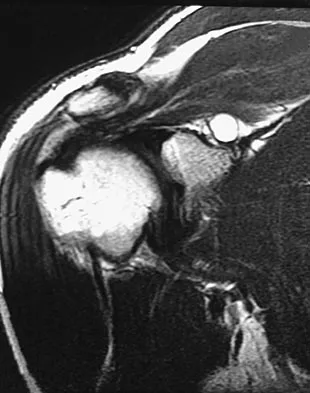

A 29-year-old man who lifts weights states that he injured his left shoulder while performing a bench press 2 days ago. The following morning he noted ecchymosis and swelling in the left chest wall. Examination reveals ecchymosis and tenderness and deformity in the left anterior chest wall and axillary fold that is accentuated with resisted adduction of the arm. Passive range of motion beyond 90 degrees of forward flexion and 45 degrees of external rotation is extremely painful. Glenohumeral stability is difficult to assess because of severe guarding. Figure 29 shows an MRI scan. Management should consist of

Explanation

Figure 47 shows a transverse MRI scan of a patient's left shoulder. The findings reveal which of the following abnormalities?

Explanation